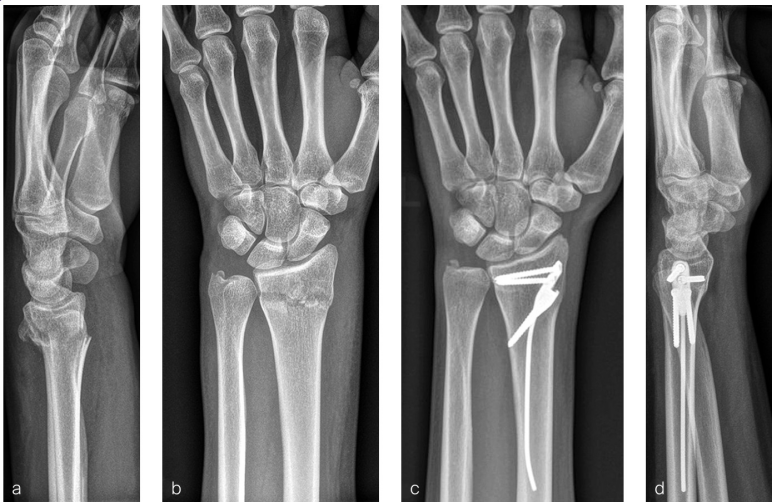

患者为一名25 岁女性,在滑雪时发生左桡骨远端移位性、不稳定型关节外骨折。

闭合复位后,发生了25ř 的背侧再脱位(见图3a)。此外,还存在其他明显的不稳定迹象:

图11 使用DRIM-Nail 的示例病例:(a)闭合复位后的术前侧位X 线片,显示与生理掌侧倾斜相比背侧脱位25ř,且伴有背侧粉碎性骨折;(b)闭合复位后的术前正位X 线片;(c)术后3 个月的正位X 线片;(d)术后3 个月的侧位X 线片,桡骨远端骨折已按解剖位置愈合。